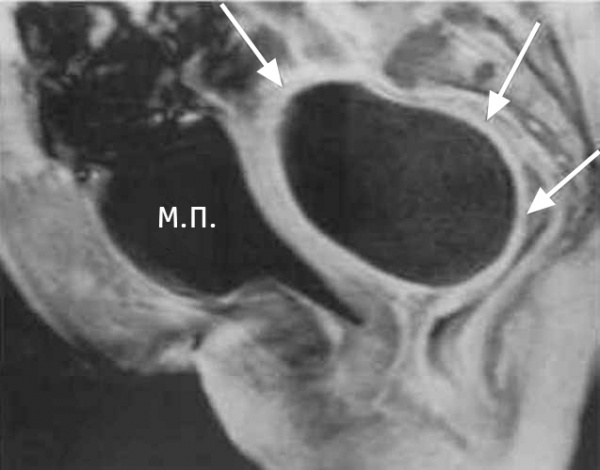

КТ-исследование абсцесса малого таза: Визуализация и диагностика

Раздел: Фотоальбом решений